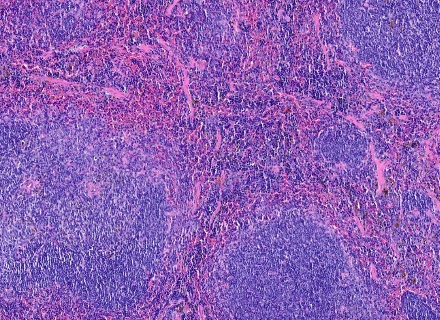

H&E staining :

Clear visualization of tissue structure

Cell distribution

Morphological changes within tissue samples

IHC Services from Our Laboratory is to detect and analyze proteins and nucleic acids across a variety of traditional and novel histopathology techniques.

With custom assay development capabilities, we can work with you to design an assay to their requirements, procure stains or antibodies, and transfer protocols.